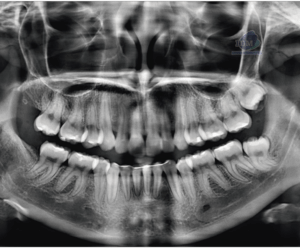

Paciente femeninos de 40 años acude a la sede IDM – Miraflores para realizarse una tomografía de campo reducido y descartar una fractura. Radiografia Panorámica